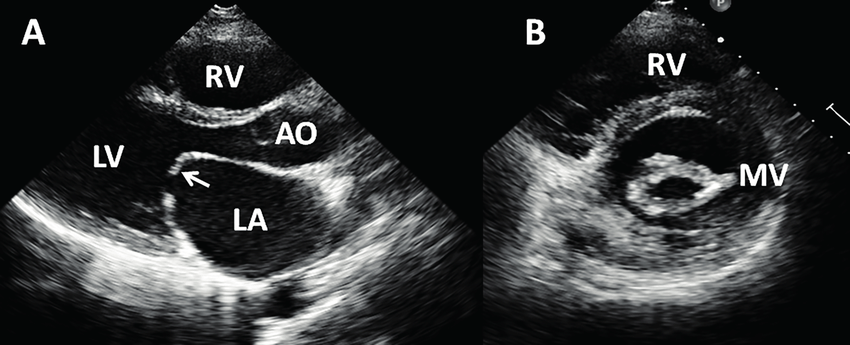

1. Mitral Stenosis

parasternal long axis view에서 ① MV의 doming & thickening, ② hockey stick appearance, ③ dilated LA

parasternal short axis view에서 "Fish-mouth appearance"